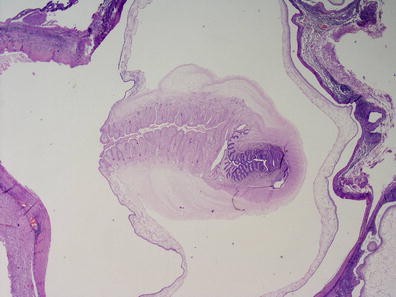

Objective: We report 10 cases of papillary carcinomas of the breast that histologically resemble PTC.

Method: These include 2 cases previously reported (Am. J. Surg. Pathol. 27, 1114–18, 2003) and 8 new cases.

Results: Patients were female of 54.7 years (mean age). All cases displayed neoplastic cells arranged in solid to papillary architectures and follicular structures resembling thyroid tissue. Cells evidenced eosinophilic granular cytoplasm and nuclei with clear chromatin with numerous grooves and occasional eosinophilic pseudoinclusions. All cases stained for mitochondria in >50 % of neoplastic elements. ER, PR, AR, Her-2, TTF1, Thyroglobulin were negative. Myoepithelial cells were absent in 8 cases. Cases were discovered mammographically, except for case 3 that had a lump present for 10 years. Sentinel nodes in 6 cases were negative. Case 3 had an intramammary metastatic lymph node. All patients are alive and well. No fewer than 3 had 10 year-FU.

Conclusion: Breast tumours resembling PTC have to be recognized to avoid misdiagnosis as metastatic PTC; they are triple negative tumours with indolent behaviour; the term tumour for these neoplasms seems appropriate as it is difficult, especially without immunohistochemistry, to establish their invasion.